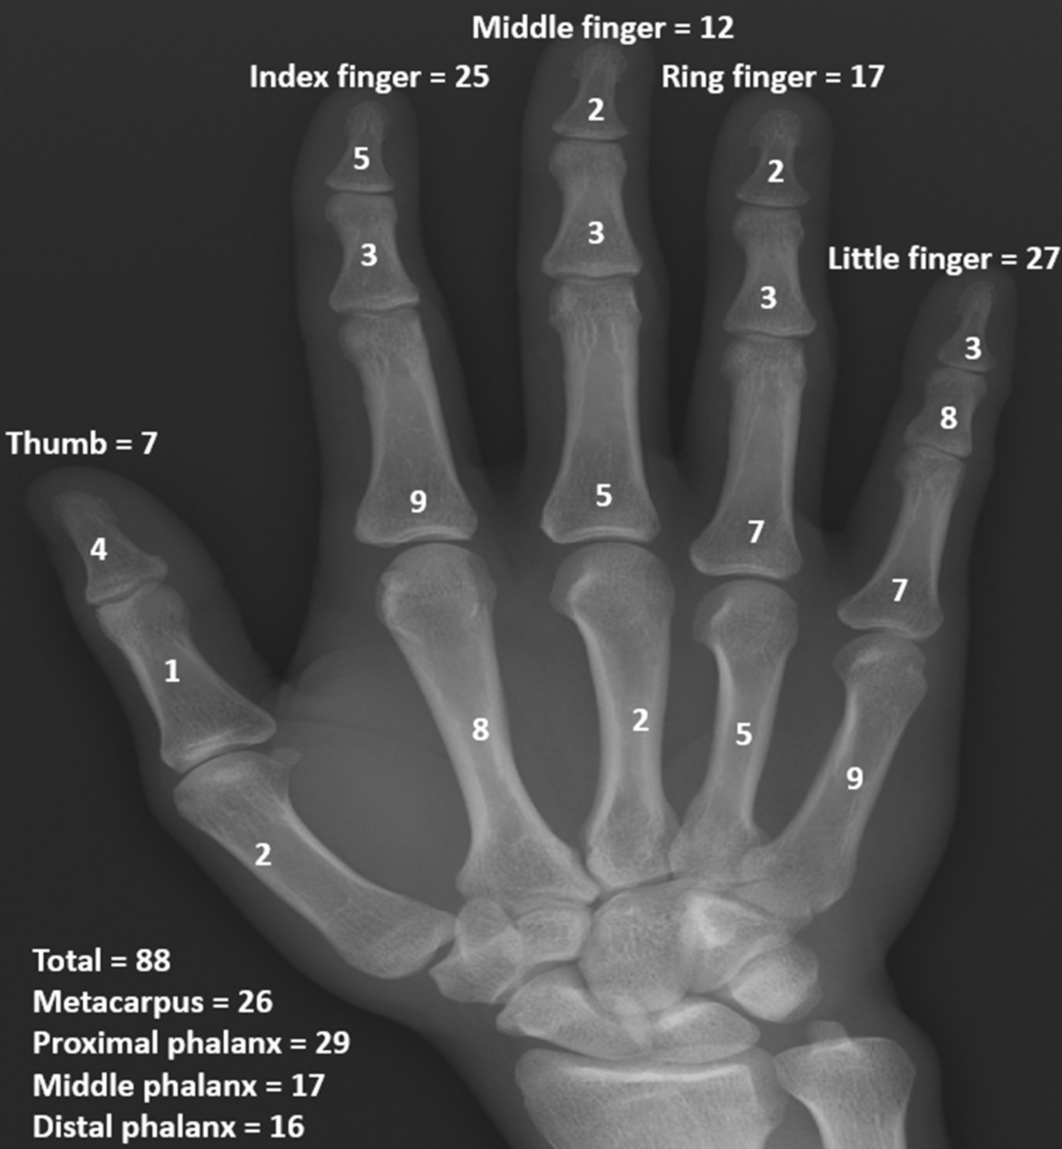

Enchondroma Hand

Enchondroma - Azouz Hand SurgeryAzouz Hand Surgery Enchondromas - Pathology - Orthobullets LearningRadiology- Enchondroma Enchondroma-of-hand LearningRadiology- Enchondroma Enchondroma Hand